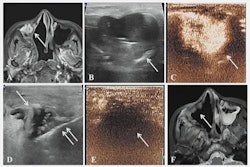

This method does not require an incision and involves real-time guidance with MRI to monitor tissue temperature while ultrasound beams are delivered to gradually heat target areas.